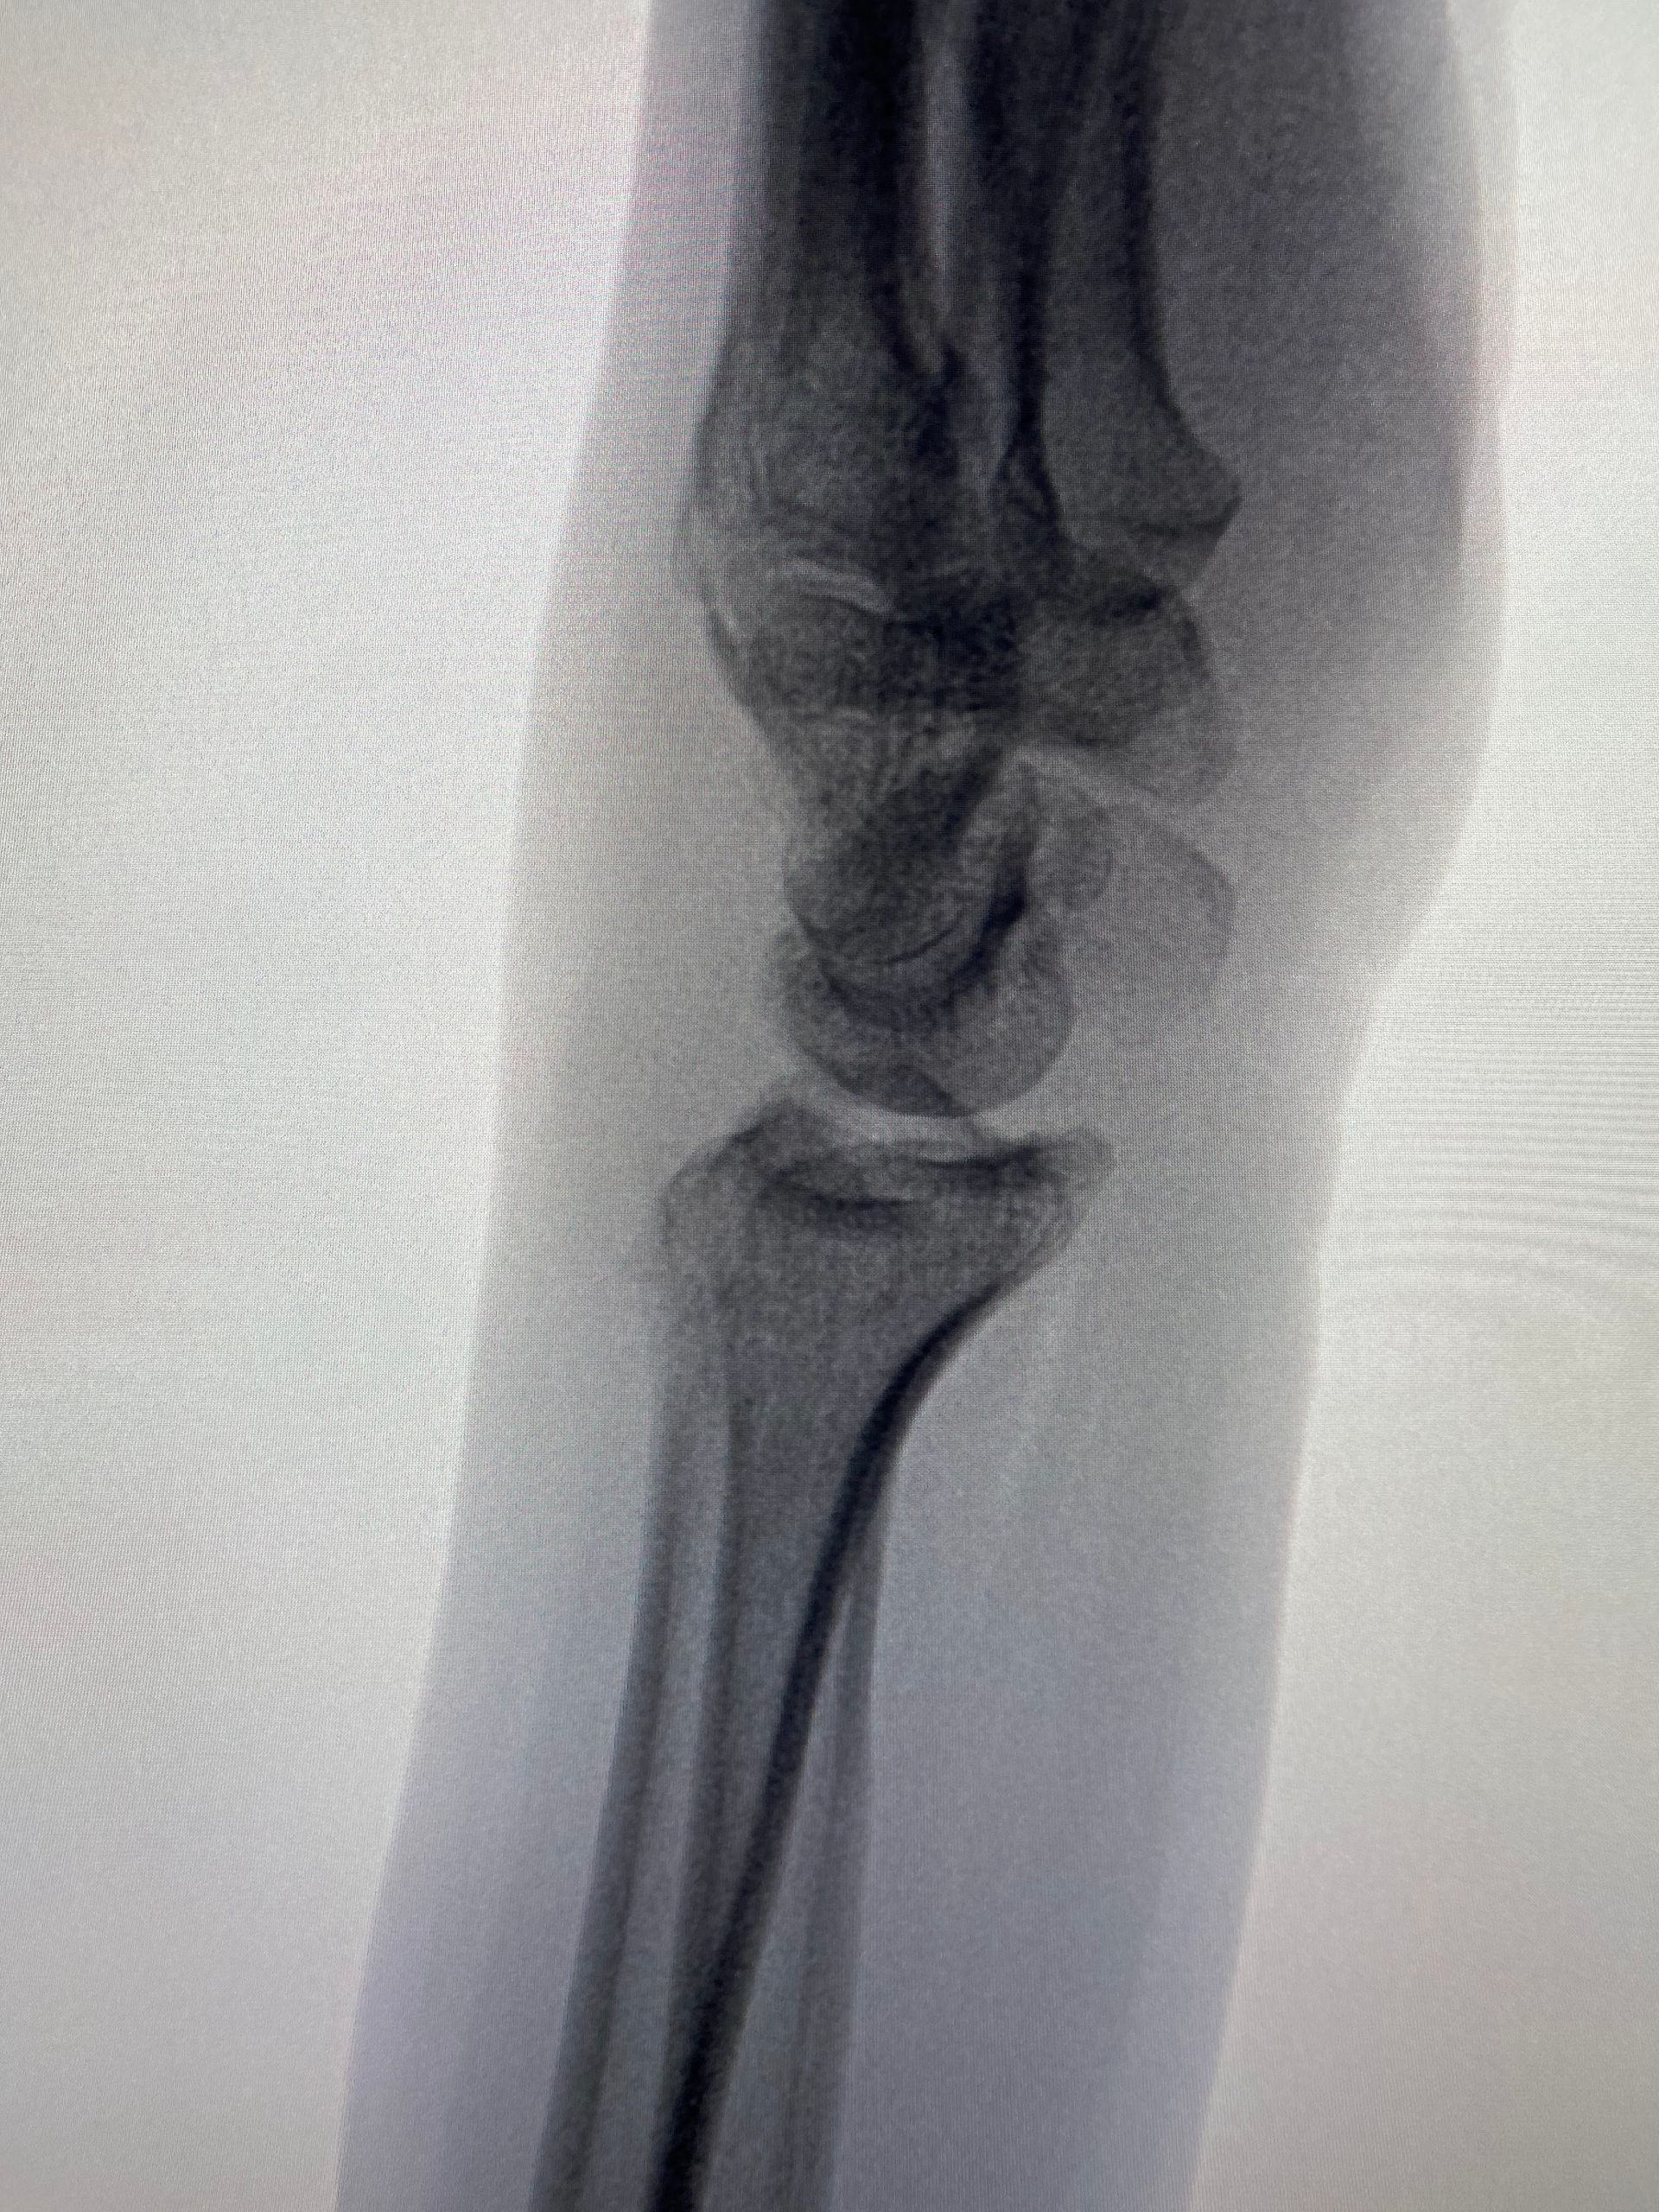

Fernandez tipo III - Fraturas compressivas articulares

- As fraturas tipo "die-punch" são causadas por um trauma axial que causa uma depressão da superfície articular, geralmente na coluna intermediária;

- A redução da fratura de modo preciso está indicada para obtermos resultados ótimos;

- A gravidade da fratura intra articular pode ser difícil de julgar somente pela radiografia, havendo indicação da tomografia computadorizada.

Sequência de imagens na avaliação inicial, radioscopia intra operatória antes da cirurgia, durante a manobra de redução com utilização de um "Freer" e após a fixação da fratura (osteossíntese). A estratégia cirúrgica utilizada envolveu, além da placa e parafusos, o uso de um parafuso canulado introduzido pela borda radial do punho, cuja função foi sustentar o fragmento articular.